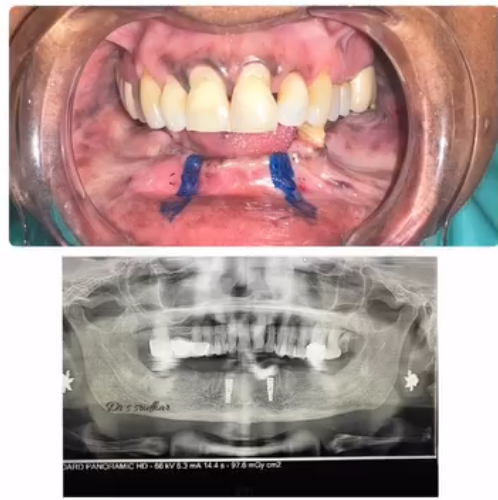

Dental Implants A permanent solution for missing teeth. Implants act as artificial tooth roots and provide superior stability and aesthetics.

High-end digital X-rays and rotary endodontics